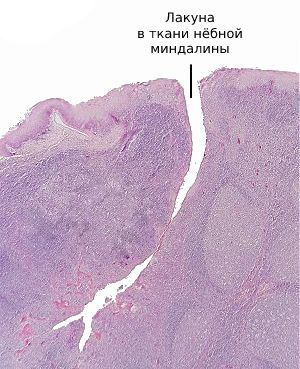

К развитию паратонзиллярного абсцесса предрасполагает сложное строение нёбных миндалин: они состоят из множества углублённых карманов (лакун), которые расположены в толще ткани и визуально напоминают фьорды.

Глубина лакун может достигать двух-трёх сантиметров. Их поверхность выстлана железами Вебера, которые механически очищают миндалины во время артикуляции, жевания и сжимания миндалин мышцами глотки при глотании, что можно сравнить с выжиманием рукой поролоновой губки.

![Лакуна в ткани нёбной миндалины [11]](/pimg3/myagkie-tkani-pri-8ACCDF.jpeg)

Снижение иммунитета, заражение патогенными бактериями, чаще всего бета-гемолитическим стрептококком, рубцы нёбных миндалин при длительном хроническом тонзиллите приводят к закупорке выводного протока желёз Вебера. Воспалительный отёк не позволяет продуктам жизнедеятельности бактерией и погибшим лимфоцитам выйти наружу в ротовую полость. В результате в ближайшей к нёбным миндалинам рыхлой клетчатке скапливается гной, который не может адекватно выйти наружу [9] [12] .